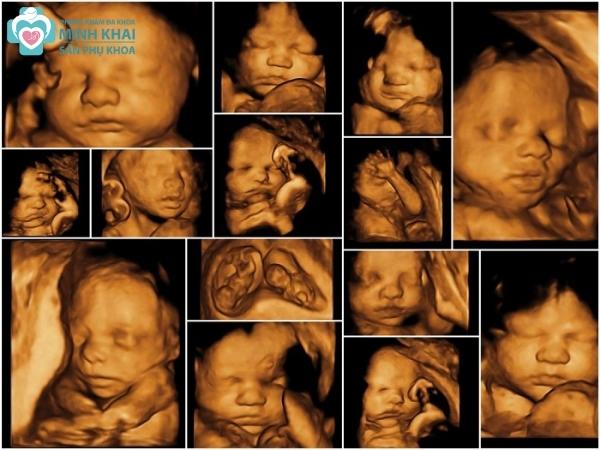

Phân tích hình ảnh siêu âm 3D trong sản khoa

Kết quả siêu âm 3D thai nhi thường có màu và rất sắc nét, nó giúp quan sát được khá nhiều góc độ của thai nhi. Do đó phân tích hình ảnh siêu âm 3D đóng vai trò quan trọng trong việc thăm khám và chẩn đoán sức khỏe thai kỳ.